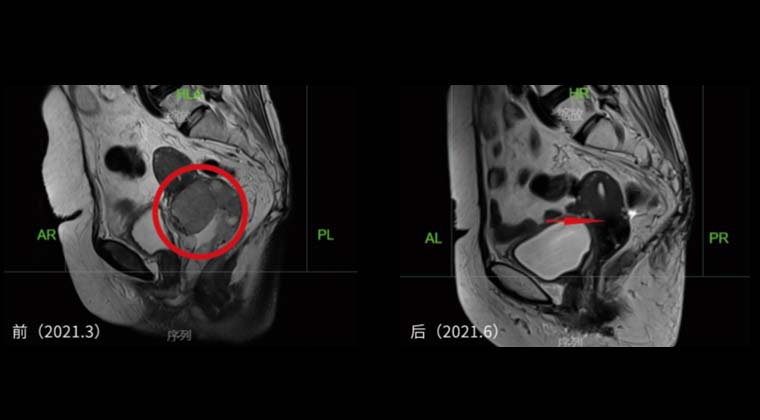

Сравнение до и после лечения показывает значительную регрессию опухоли и её исчезновение.

Рисунок 1: План лечения внешним облучением + брахитерапией с дистанционным введением источника

Рисунок 2 слева: До лечения

Рисунок 2 справа: После лечения